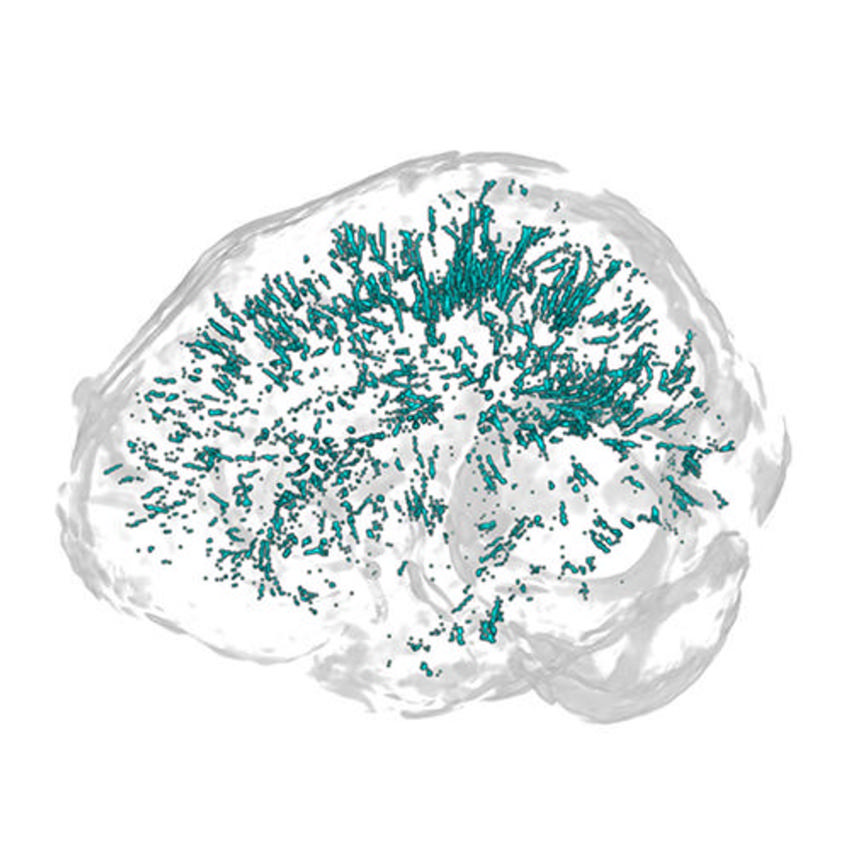

Figure 3. A 3D map of centrum semiovale (CSO) and basal ganglia (BG) perivascular spaces (PVS) generated from physician-reviewed automated segmentation of PVS using ITK-SNAP software.